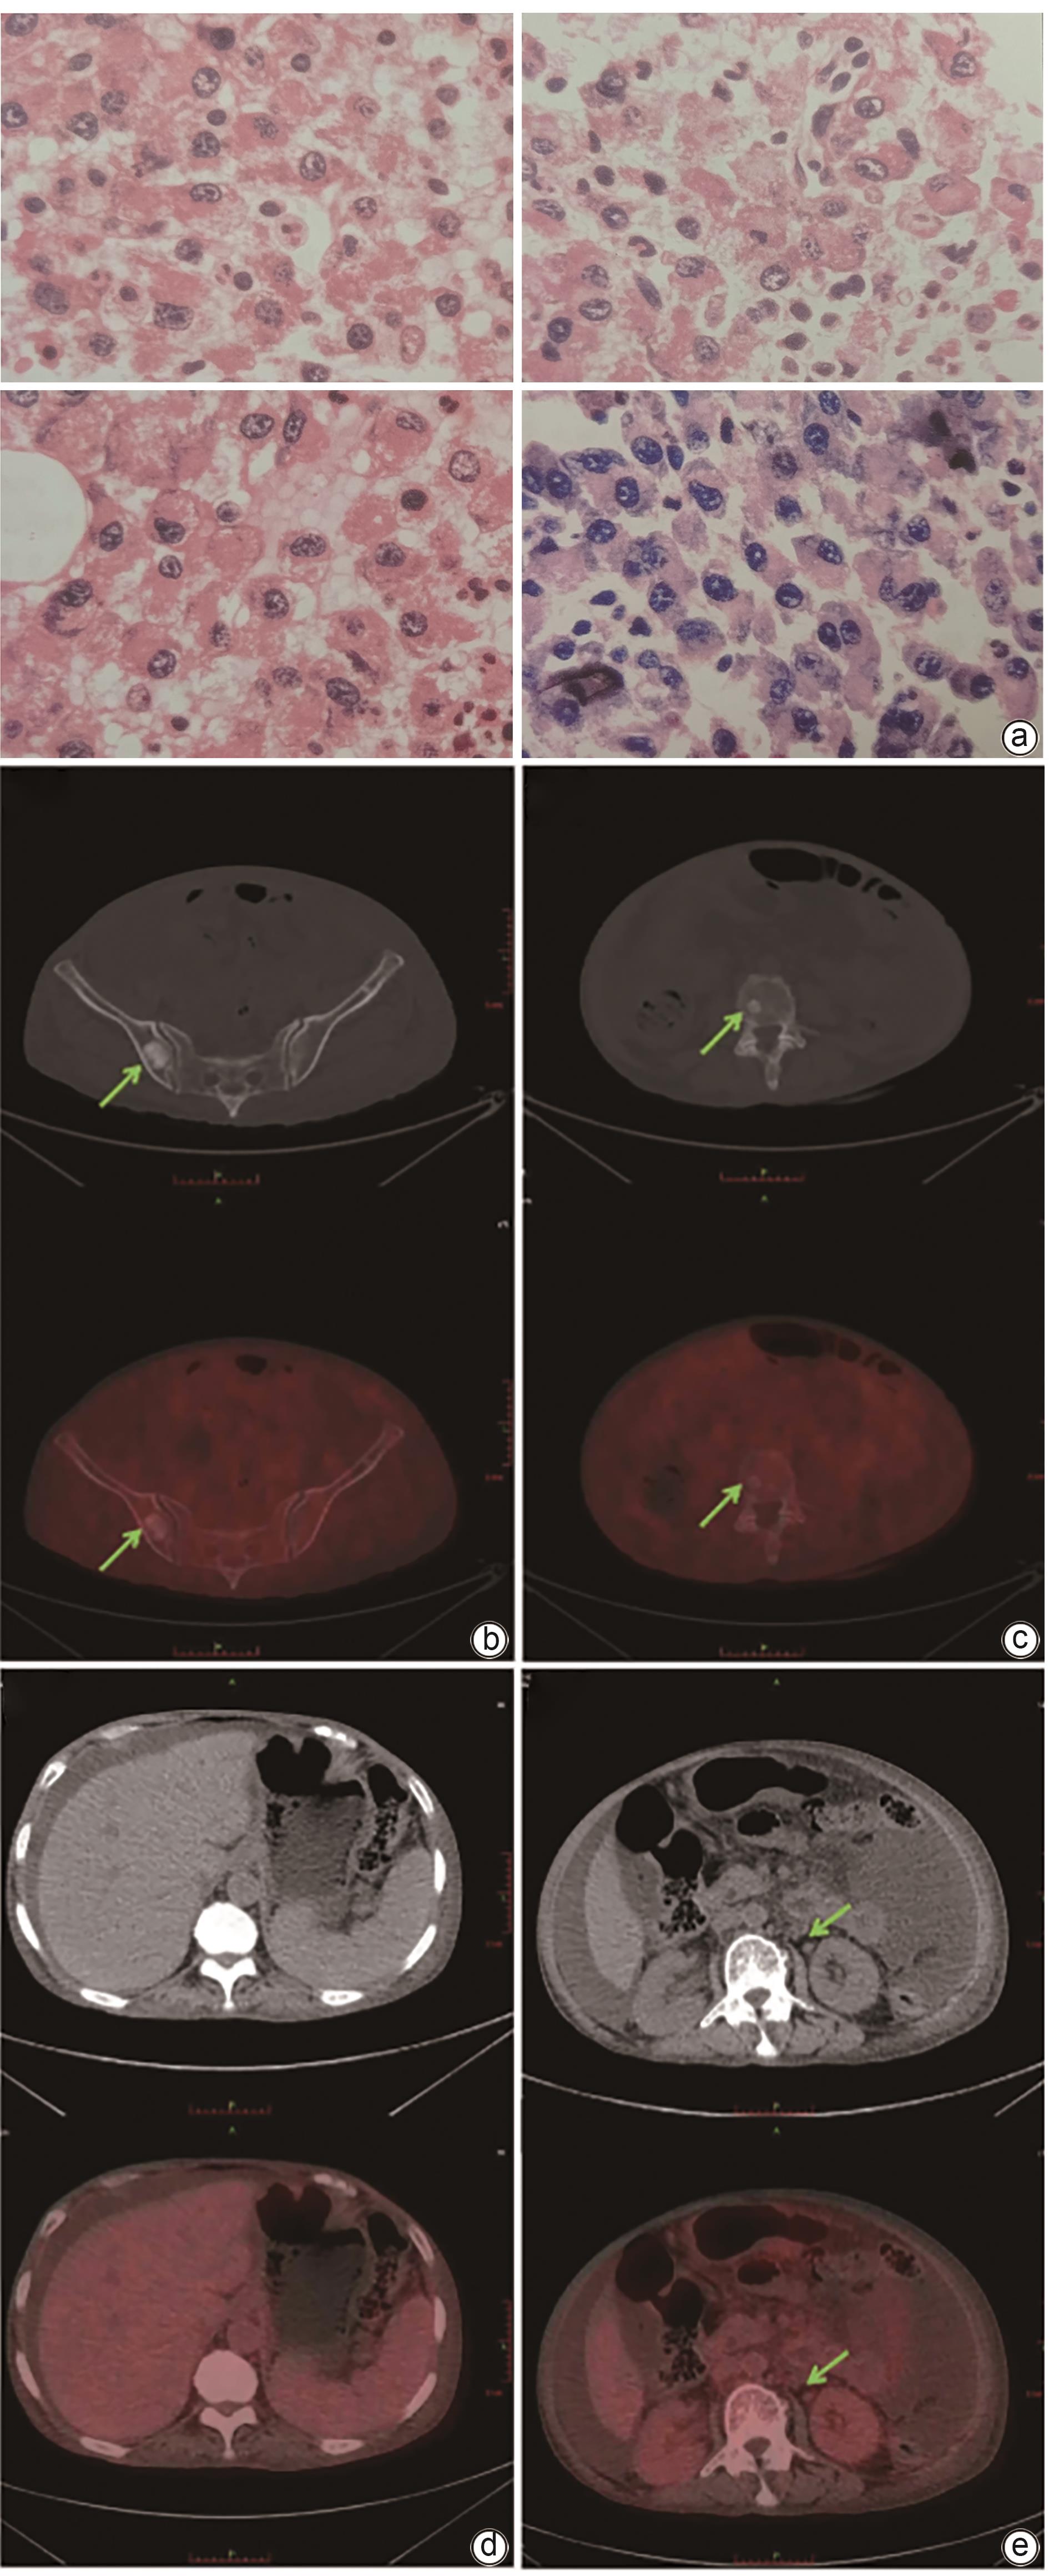

POEMS syndrome with hepatosplenomegaly as the initial manifestation: A report of two cases

Ye ZHANG, Wenqing WANG, Jing LI, Qianrong BAI, Jiayu LI, Yan CHENG, Miaomiao FANG, Nana GAO, Changxing HUANG

2025, 41(1): 127-132. DOI: 10.12449/JCH250119

Abstract(968) HTML (257) PDF (2190KB)(84)

Abstract:

POEMS syndrome is a rare condition associated with plasma cell disorders, and it often involves multiple systems and has diverse clinical manifestations. This article reports two cases of POEMS syndrome with hepatosplenomegaly as the initial manifestation. During the course of the disease, the patients presented with lower limb weakness, hepatosplenomegaly, lymph node enlargement, ascites, hypothyroidism, positive M protein, and skin hyperpigmentation, and 18F-FDG PET-CT imaging revealed bone lesions mainly characterized by osteolytic changes and plasma cell tumors. There was an increase in the serum level of vascular endothelial growth factor. The patients were finally diagnosed with POEMS syndrome, and the symptoms were relieved after immunomodulatory treatment.